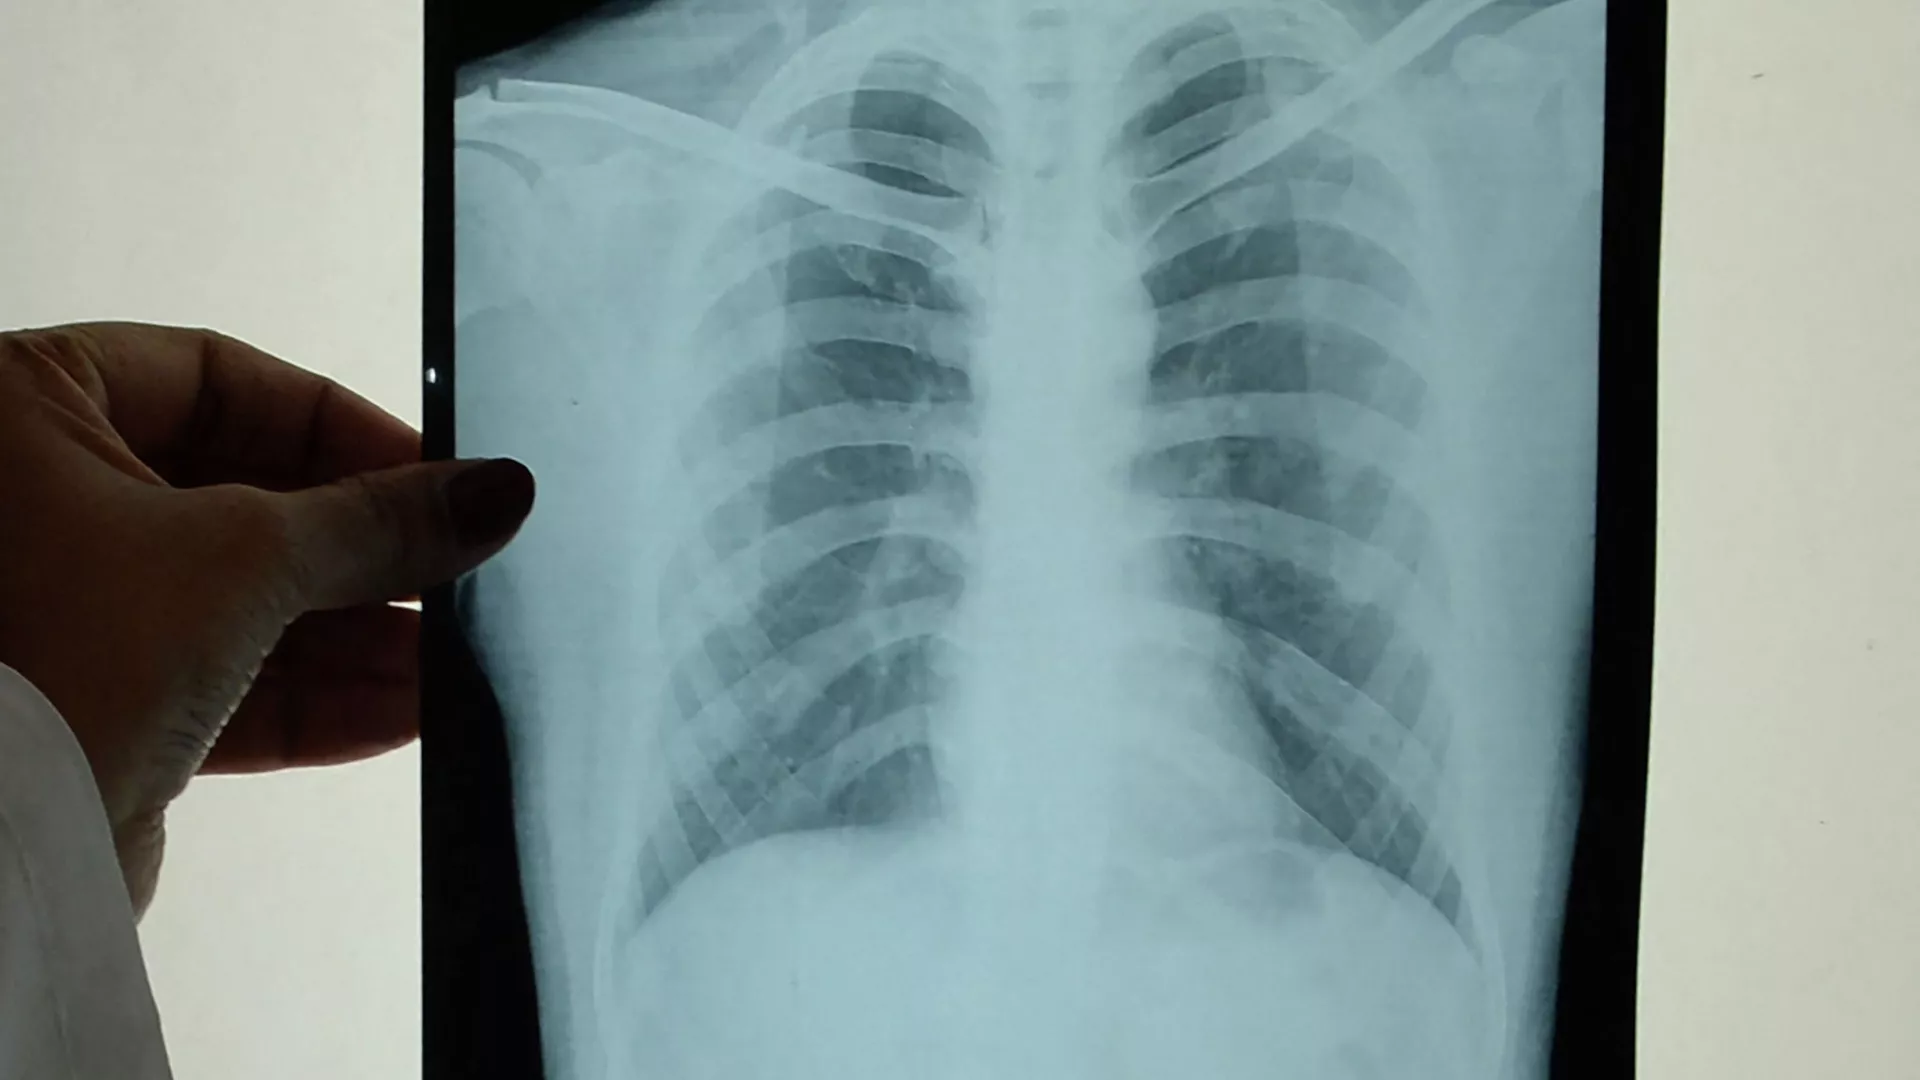

— Биринчи эле какырык тапшырат. Ал бардык аймакта бекер жасалат. Экинчиден, өпкөсүн рентгенге тарттырат. Ушул эки жолу менен эле аныктап коёт.